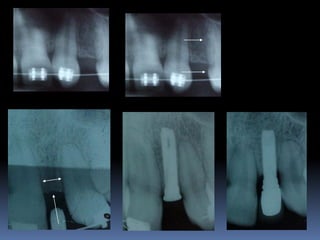

Exames Imaginológicos

Radiografias periapicais, telerradiografias e

panorâmicas;

Tomografias computadorizadas

Softwares de imagens 3D